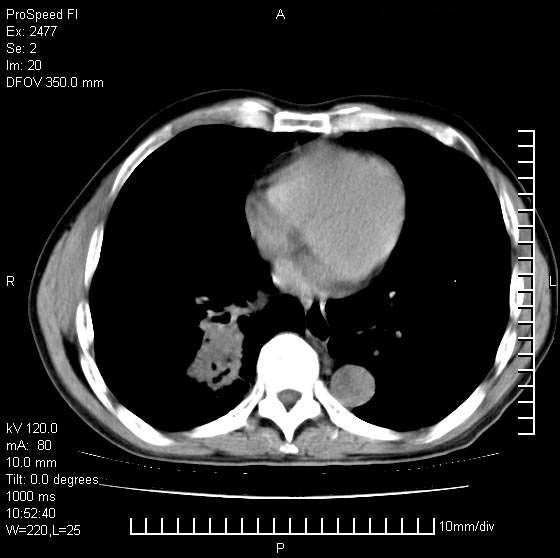

以下是引用天南地北在2007-10-9 14:29:00的发言:[br]1:右上肺结核[br]2:右肺下叶肿块:不支持肺癌,首先考虑炎性病变-肺脓疡可能性大[br]理由:1:临床病史支持,肺脓肿症状不明显应该是不规则服药造成。[br] 2:肿块边缘模糊,周围可见炎性渗出,长毛刺,内见支气管征,不过有点不规则。[br] 我感觉下肺癌这个诊断有点偏左,建议积极抗炎治疗后复查

以下是引用卜一在2007-10-9 15:55:00的发言:[br][br] [br] 1:右上肺结核[br]2:右肺下叶肿块:不支持肺癌,首先考虑炎性病变-肺脓疡可能性大[br]理由:1:临床病史支持,肺脓肿症状不明显应该是不规则服药造成。[br] 2:肿块边缘模糊,周围可见炎性渗出,长毛刺,内见空气支气管征,不过有点不规则。[br] 我感觉下肺癌这个诊断有点偏左,建议积极抗炎治疗后复查![br]支持! [br] [br] [br]

以下是引用wxy7406在2007-10-9 21:02:00的发言:[br]结合临床病史首先考虑感染性病变,但周围型肺癌不能除外,1.患者年龄偏大2.临床有咯血3.(也觉得是最重要的一点)病灶内有偏心性空洞。

以下是引用王仕学在2007-10-9 13:48:00的发言:[br]右下肺周围性肺癌可能性大,最好活检吧

以下是引用hhcckk在2007-10-9 15:18:00的发言:[br]右上肺病灶考虑结核,病灶多种形态并存(纤维化、增殖性病灶并存)[br]右下肺病灶比较难说,个人意见更趋向于“天南地北”的诊断----肺脓肿[br]1、病人有明显的寒战,高热,肿瘤病人很少出现[br]2、病灶周围的肺纹理走向柔和,没有肿瘤病灶常见的集束征[br]3、病灶边缘的毛刺较长,恶性肿瘤多为短毛刺[br]痰中血丝和病人的年龄是两个不利于良性肿块的因素,建议早点活检

以下是引用ydx_74在2007-10-9 15:53:00的发言:[br]右上肺结核,右下中心性肺癌可能大,肺门淋巴结肿大。